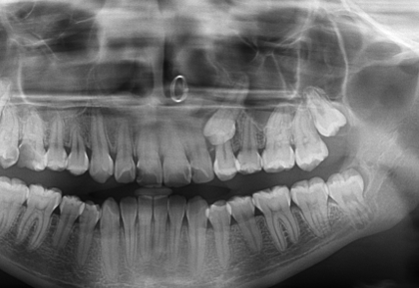

La presentación de casos radiográficos, permite la visualización de patologías que son muy difíciles de ver en la clínica, ya que muchos de ellos son hallazgos radiográficos. Además permite ver y refrescar clasificaciones y conceptos muchas veces estudiados. La presentación de los mismos no incluyen datos personales, mas que edad y sexo, que suelen ser importantes para ver la correlación entre la patología, su aparición o forma de presentación.

Esto también refleja las patologías que aquejan a los pacientes de nuestra región, y trata de ser un faro tanto para profesionales como alumnos que estudian dichas lesiones.